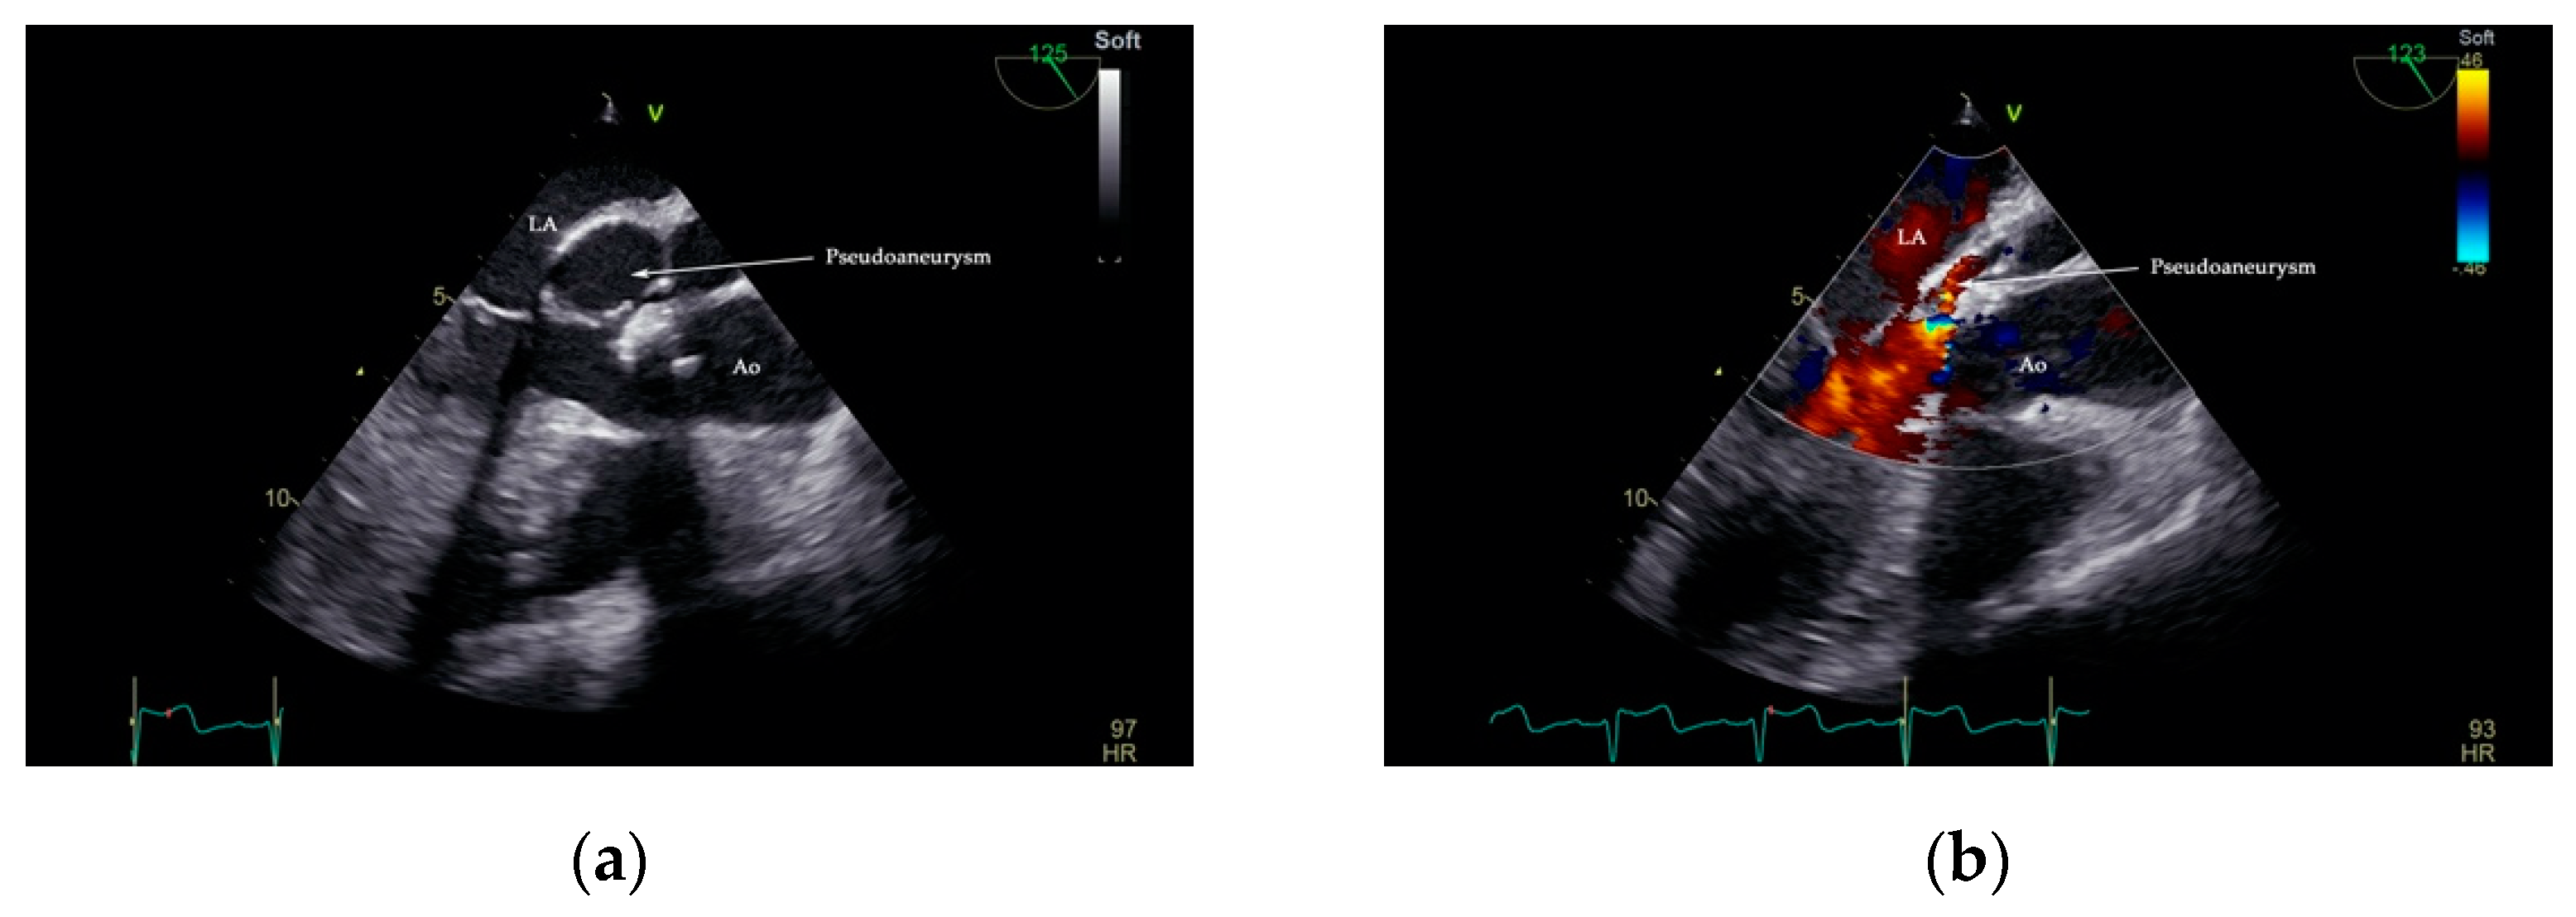

Interpretation of TOE images digitally archived in DICOM format confirmed the presence of an echo-lucent space that displayed a characteristic systolic expansion and a diastolic collapse, and a posterior aortic-oriented communication with LVOT between the left atrium, mitral valve, and aortic valve. Color flow Doppler visualized a highly turbulent flow in the pseudoaneurysm (Figure 4, Supplementary Movie S2, and S2.1).

Figure 4.

Two-dimensional TOE showing the presence of pseudoaneurysm of the mitral-aortic intervalvular fibrosa (P-MAIVF). Arrow—pseudoaneurysm lumen in systole (a). A turbulent flow seen in the pseudoaneurysm lumen during diastole (b). Ao—aorta, LA—left atrium.